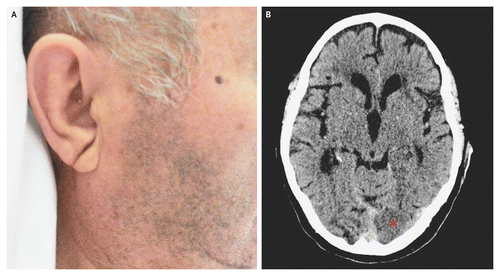

Σύμφωνα με μερικές μελέτες, το ποσό της τρίχας που έχετε στα αυτιά σας μπορεί να αποτελεί ένδειξη της μελλοντικής υγείας της καρδιάς σας. Γιατί αυτό; Μερικοί ερευνητές και γιατροί προσπαθούν να το εξακριβώσουν εδώ και δεκαετίες, και εξηγείται παρακάτω. Αφήστε κάτω τα τσιμπιδάκια και αρχίστε να ενημερώνεστε επάνω σε αυτό. Η κατανόηση του πώς οι τρίχες στα αυτιά σας συνδέονται με την υγεία της καρδιάς σας μπορεί πιθανότατα να σώσει τη ζωή σας.

Οι τρίχες στα αυτιά μπορεί να είναι κακό σημάδι – και όχι επειδή δεν είναι και τόσο όμορφο θέαμα.

Σύμφωνα με μια πρόσφατη μελέτη, υπάρχει σύνδεση μεταξύ των τριχών στο κανάλι του αυτιού και τις καρδιακές προσβολές.

Το 1973, ο Δρ. Sanders T. Frank και η ομάδα του κατέγραψαν πως μια διαγώνια τσάκιση στο λοβό του αυτιού μπορεί να σηματοδοτεί κάποια στεφανιαία αρτηριακή πάθηση. Το 1984, μια άλλη επιστημονική ομάδα επανέφερε την ίδια θεωρία.

Το 2016 ο Δρ. Edston E. δημοσίευσε μια έρευνα στην Αμερικανική εφημερίδα της ιατροδικαστική ιατρικής παθολογίας. Δήλωνε πως η τσάκιση στον λοβό ενός αυτιού ήταν ισχυρά συνδεδμένη με καρδιακές παθήσεις σε άντρες και γυναίκες.